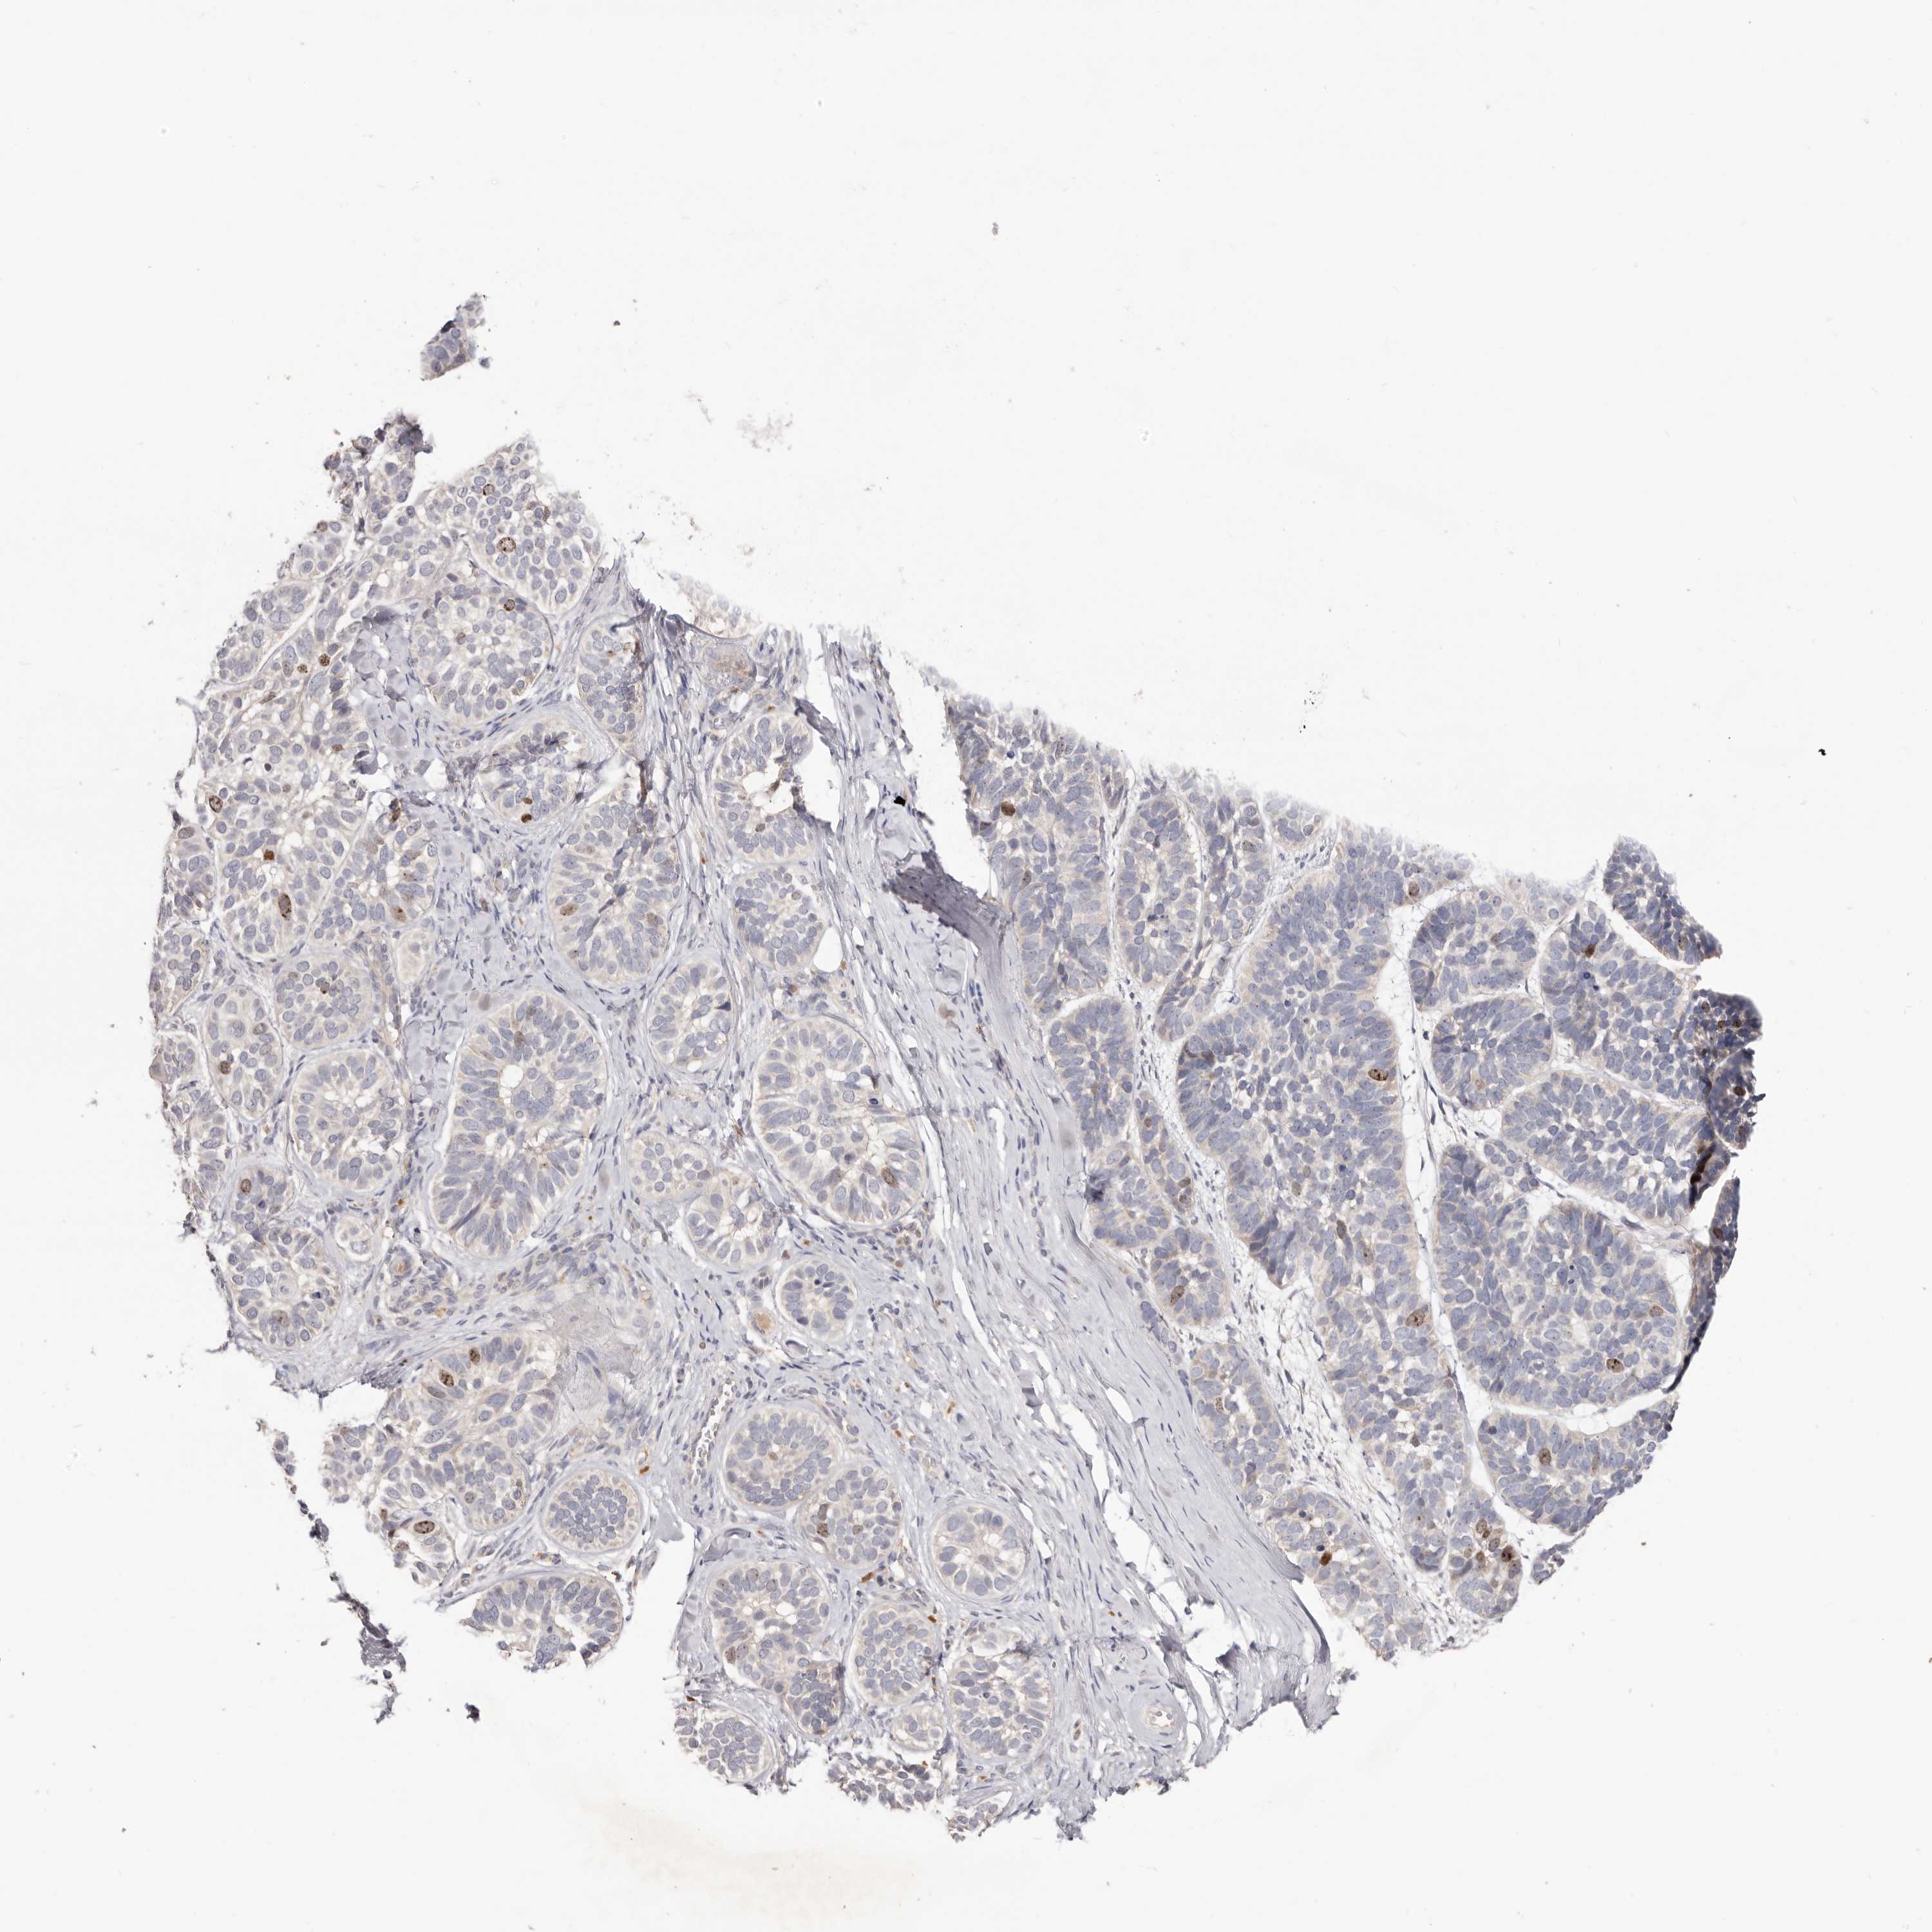

SKIN CANCER - Protein expressioni

A mouse-over function shows sample information and annotation data. Click on an image to view it in a full screen mode. Samples can be filtered based on level of antibody staining by selecting one or several of the following categories: high, medium, low and not detected. The assay and annotation is described here.

Each image is clickable and will lead to virtual microscopy that enables deeper exploration of all samples and also displays staining intensity scores, fraction scores and subcellular localization as well as patient and tissue information for each sample.

Antibody HPA028592

Staining

High

Medium

Low

Not detected

Intensity

Strong

Moderate

Weak

Negative

Quantity

>75%

75%-25%

<25%

None

Location

Nuclear

Cytoplasmic/membranous

Cytoplasmic/membranous,nuclear

Squamous cell carcinoma, NOS